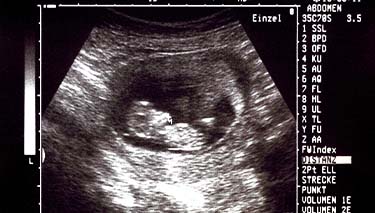

What to expect during your 9 week ultrasound

This ultrasound may be conducted vaginally or externally on your abdomen. Know that if your healthcare professional has officially referred you for an early scan Medicare will cover it.

At nine weeks, you will be able to see your baby's head, body and limbs. You will also be able to hear your little one's heart beat for the first time with a Doppler monitor. Bring some tissues with you; this can be a very emotional moment.

At nine weeks, your baby will measure approximately 2.5 centimetres. The foetus will resemble a green olive and weigh less than 2 grams.

Your little one's eyes will have grown larger and even have some colour, but their eyelids will still be fused shut. Your ultrasound may be able to show you the beginnings of what will be your little one's fingers and toes too.